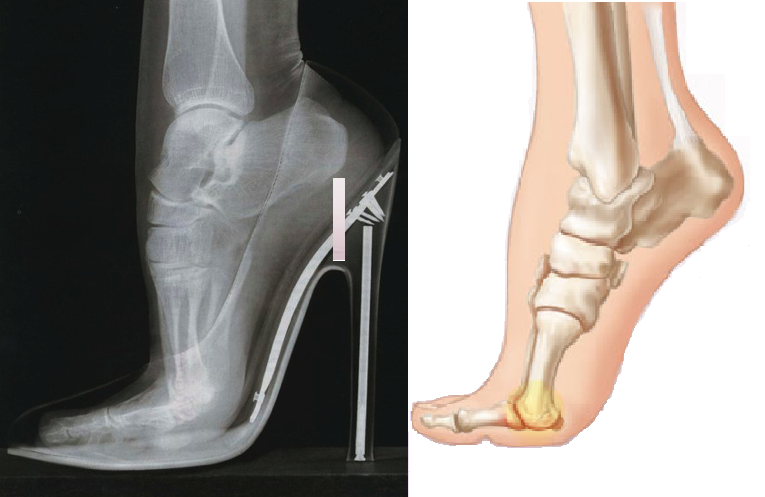

High Heels – High Risk of Aches & Pains

High Heels – High Risk of Aches & Pains 𝐖𝐡𝐢𝐜𝐡 𝐏𝐚𝐫𝐭𝐬 𝐨𝐟 𝐌𝐲 𝐁𝐨𝐝𝐲 𝐖𝐢𝐥𝐥 𝐁𝐞 𝐀𝐟𝐟𝐞𝐜𝐭𝐞𝐝 𝐛𝐲 𝐇𝐢𝐠𝐡 𝐇𝐞𝐞𝐥𝐬? […]